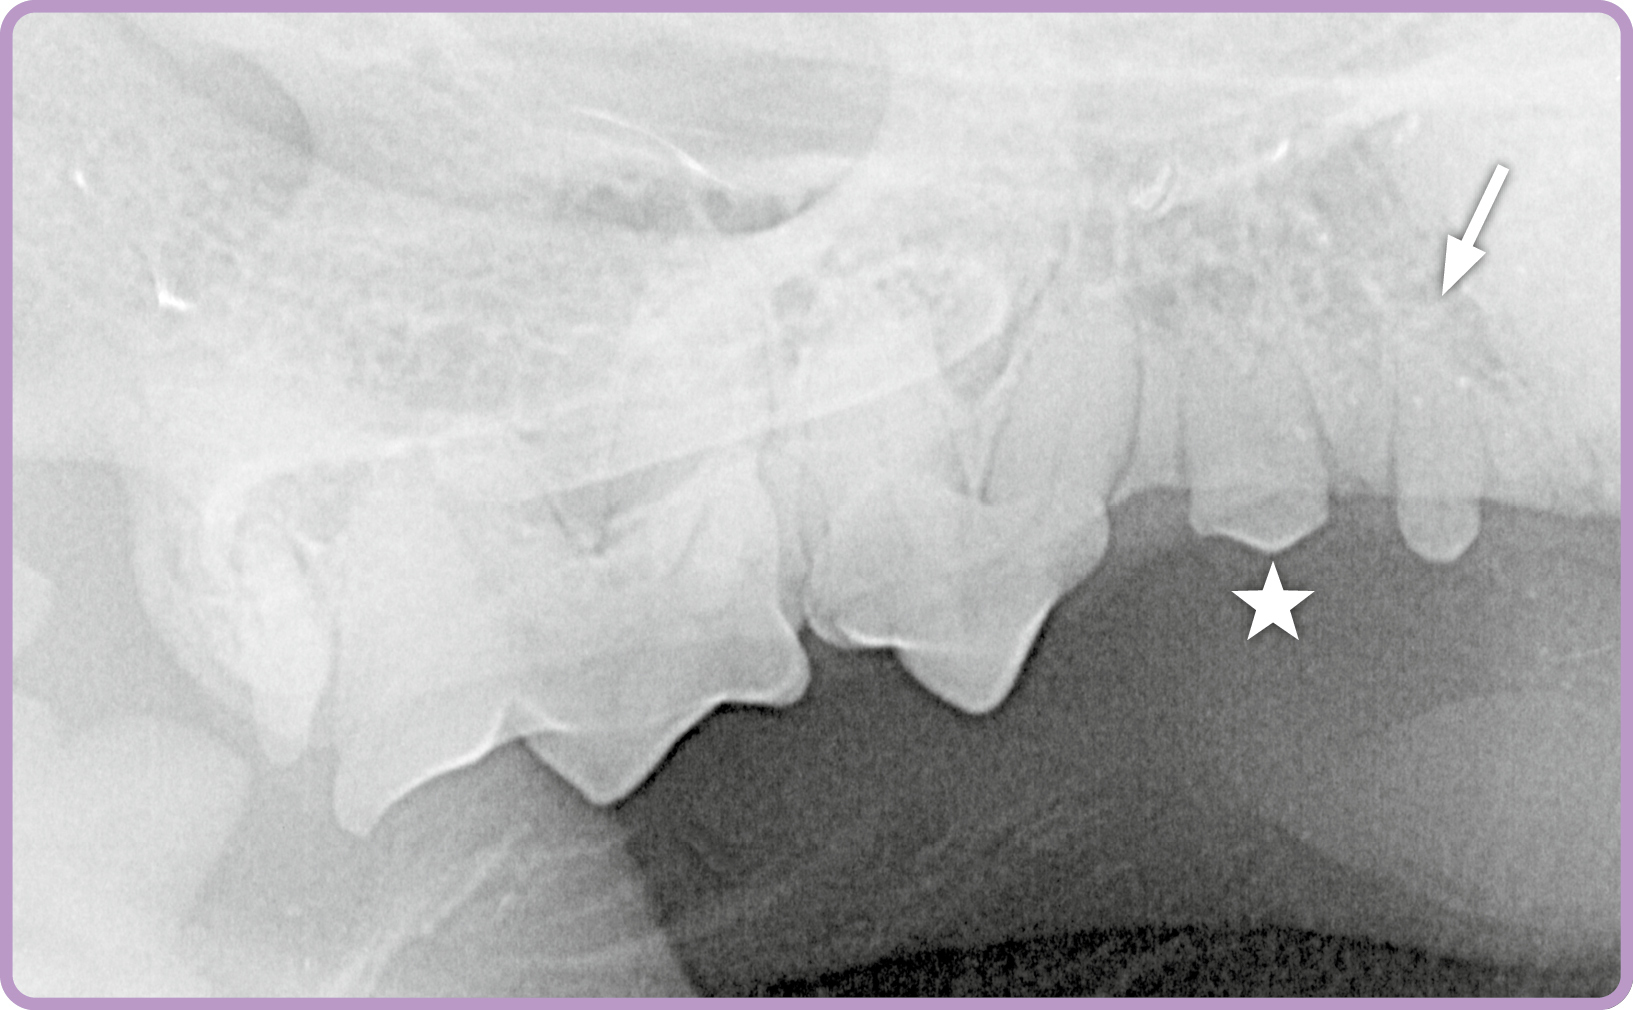

Röntgenbeispiel Katze: Die Aufnahme einer Katze (Abb. 1) zeigt eine überzählige Wurzel des zweiten Prämolaren (⭐️) im Oberkiefer rechts. Darüber hinaus wird auch ein zusätzlich angelegter Zahn im Bereich des zweiten Prämolaren

sichtbar (➡️).